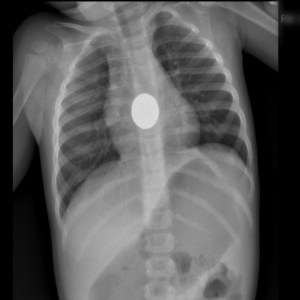

- Si los padres están muy asustados o, por supuesto, si el niño no está bien, se debe acudir a un Servicio de Urgencias Pediátricas, donde si se estima oportuno, se le hará una radiografía. Esta permitirá saber si la tragó o no. La radiografía es muy útil en estos casos. Las monedas se ven muy bien en una radiografía de tórax (ojo, no se ven otros objetos como juguetes de plástico, etc).

Cuando se demuestra en una radiografía que efectivamente se aprecia la moneda en el intestino del niño, y éste se encuentra bien, sólo nos queda esperar a que la expulse en las heces. En caso de no hacerlo en el tiempo de más de una semana, debemos acudir al pediatra para una reevaluación.

Ésta es una imagen de la radiografía de una niña de 20 meses tras ingesta accidental de una moneda en el momento del diagnóstico. Por la posición alta de la moneda, se planteó en un primer momento, su extracción mediante endoscopia digestiva, que finalmente no precisó, observándose que expulsó la moneda en heces sin llegar a presentar ningún síntoma.